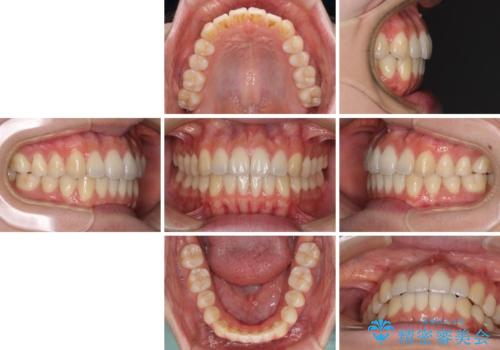

オープンバイトでかみにくい インビザラインによる矯正治療

- 前歯の上下スペースによる食べにくさを気にして来院された患者様です。

インビザラインにより上下の前歯の隙間を閉じていくこととしました。

上下の奥歯を圧下させるようにすることで、前歯を接触させるように計画しました。

上下の隙間に舌が入り込むことがオープンバイトの原因であったため、舌の筋肉のトレーニングも並行して行い、後戻りの抑制を図りました。